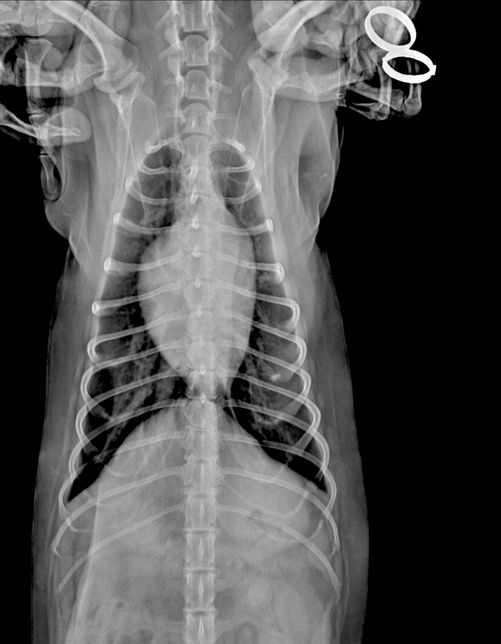

- 반려동물 건강반려동물Q. (이은수 수의사님) 하나만 더 여쭤보고싶습니다ㅠ 강아지 엑스레이 관련안녕하세요 강아지 건강검진 받고 엑스레이상 흉골이 휘었다고 했었는데요, 외부충격은 없고, 1년 전 다른 병원에서 찍은 엑스레이는 흉골 휘지 않았습니다. 사진상으로 휘어보이는거라고 하셨는데 잘못찍혔다는 말씀이실까요? 건강검진 병원에서는 1년전 다른 병원에서 찍은 엑스레이는 흉골이 휘지 않아서 폐쪽 문제일수도 있으니 ct가능한 병원가서 정확하게 보는게 좋을거같다는데, 폐에 문제가 생기면 심장이 쏠리면서 흉골이 휠수도있나요..? 엑스레이는 흉골이 휜거같아 이상해서 세번정도 찍었다고 하네요. 사진 보면 노란색 표시 흉골이 휘어있고 심장도 쏠려있습니다…잘못찍었다고 흉골이 휘고 심장도 쏠릴 수 있나요?!?첫번째 사진이 1년전 다른병원에서 찍은 엑스레이고 2,3번째가 이번에 찍은 흉골 휜 엑스레이입니다.. 3,4번째 흉골 휜 엑스레이 같은 사진인데 휜 흉골부분 노란색으로 표시해뒀습니다. R, L사진 둘 다 다른방향에서 찍은거같은데, 둘 다 휘어있습니다. 폐쪽의 문제일수도 있을까요? 기침이나 식욕감퇴 등의 다른 증상은 없고 변 상태도 좋습니다.

- 반려동물 건강반려동물Q. 강아지 엑스레이 잘못찍으면 흉골 휘어보이게 나오는건가요안녕하세요 강아지 건강검진 받고 엑스레이상 흉골이 휘었다고 했었는데요, 외부충격은 없고, 1년 전 다른 병원에서 찍은 엑스레이는 흉골 휘지 않았습니다. 사진상으로 휘어보이는거라고 하셨는데 잘못찍혔다는 말씀이실까요? 건강검진 병원에서는 1년전 다른 병원에서 찍은 엑스레이는 흉골이 휘지 않아서 폐쪽 문제일수도 있으니 ct가능한 병원가서 정확하게 보는게 좋을거같다는데, 폐에 문제가 생기면 심장이 쏠리면서 흉골이 휠수도있나요..? 엑스레이는 흉골이 휜거같아 이상해서 세번정도 찍었다고 하네요. 사진 보면 노란색 표시 흉골이 휘어있고 심장도 쏠려있습니다…잘못찍었다고 흉골이 휘고 심장도 쏠릴 수 있나요?!?첫번째 사진이 1년전 다른병원에서 찍은 엑스레이고 2,3번째가 이번에 찍은 흉골 휜 엑스레이입니다.. 3,4번째 흉골 휜 엑스레이 같은 사진인데 휜 흉골부분 노란색으로 표시해뒀습니다. R, L사진 둘 다 다른방향에서 찍은거같은데, 둘 다 휘어있습니다. 폐쪽의 문제일수도 있을까요? 기침이나 식욕감퇴 등의 다른 증상은 없고 변 상태도 좋습니다.

- 반려동물 건강반려동물Q. 강아지 엑스레이 흉골이 휘었다는데오안녕하세요 강아지 건강검진 받고 엑스레이상 흉골이 휘었다고 했었는데요, 외부충격은 없고, 1년 전 다른 병원에서 찍은 엑스레이는 흉골 휘지 않았습니다. 사진상으로 휘어보이는거라고 하셨는데 잘못찍혔다는 말씀이실까요? 건강검진 병원에서는 1년전 다른 병원에서 찍은 엑스레이는 흉골이 휘지 않아서 폐쪽 문제일수도 있으니 ct가능한 병원가서 정확하게 보는게 좋을거같다는데, 폐에 문제가 생기면 심장이 쏠리면서 흉골이 휠수도있나요..? 엑스레이는 흉골이 휜거같아 이상해서 세번정도 찍었다고 하네요. 사진 보면 노란색 표시 흉골이 휘어있고 심장도 쏠려있습니다…잘못찍었다고 흉골이 휘고 심장도 쏠릴 수 있나요?!? 첫번째 사진이 1년전 다른병원에서 찍은 엑스레이고 2,3번째가 이번에 찍은 흉골 휜 엑스레이입니다.. 3,4번째 흉골 휜 엑스레이 같은 사진인데 휜 흉골부분 노란색으로 표시해뒀습니다. R, L사진 둘 다 다른방향에서 찍은거같은데, 둘 다 휘어있습니다. 폐쪽의 문제일수도 있을까요? 기침이나 식욕감퇴 등의 다른 증상은 없고 변 상태도 좋습니다.

- 반려동물 건강반려동물Q. 강아지 엑스레이 흉골 휘었다는데요 ..안녕하세요 강아지 건강검진을했는데 흉골이 휘었다고해서요. 첫번째사진은 1년전이고 2,3번째 사진은 이번년도 사진입니다. 혹시 이런경우 원인은 무엇인가요? 외부충격은 없었습니다..

- 반려동물 건강반려동물Q. 강아지 엑스레에 찍을 때 자세 이상하면 흉골이 휘어보이게 나올수도 있나요? 강아지 엑스레에 찍을 때 자세 이상하면 흉골이 휘어보이게 나올수도 있나요? 건강검진 했는데 흉골이 휘었대서요.. 작년 다른 병원에서 검진했을 때는 괜찮았는데 외부충격도 없었는데 1년만에 휘을수가있나요.?.. 외부 충격 아니면 폐쪽 문제일수도있다는데 외부충격은 없었고, 기침이나 다른 증상도 없어서요. 혹시 엑스레이 찍을 때 자세가 잘못되면 흉골이 휘게 나오기도 하나요